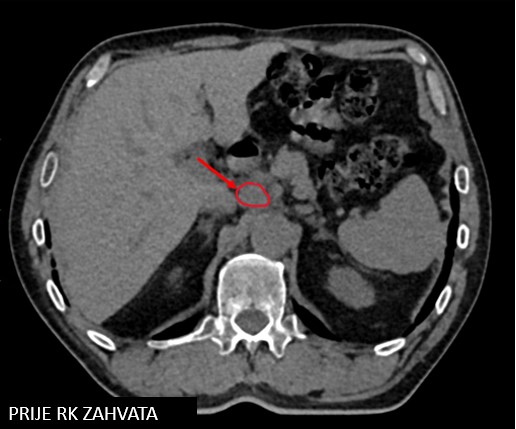

Meta hepatis

Meta lymphonodi intraabdominalis (uz truncus celiacus)

SBRT lymphonodi intraabdominalis (22.11. - 26.11.2021.)

SABR meta hepatis (16.03.-24.03.2023.)

Rezultat – 19 mjeseci nakon RK

Potpuni nestanak tretiranog limfnog čvora